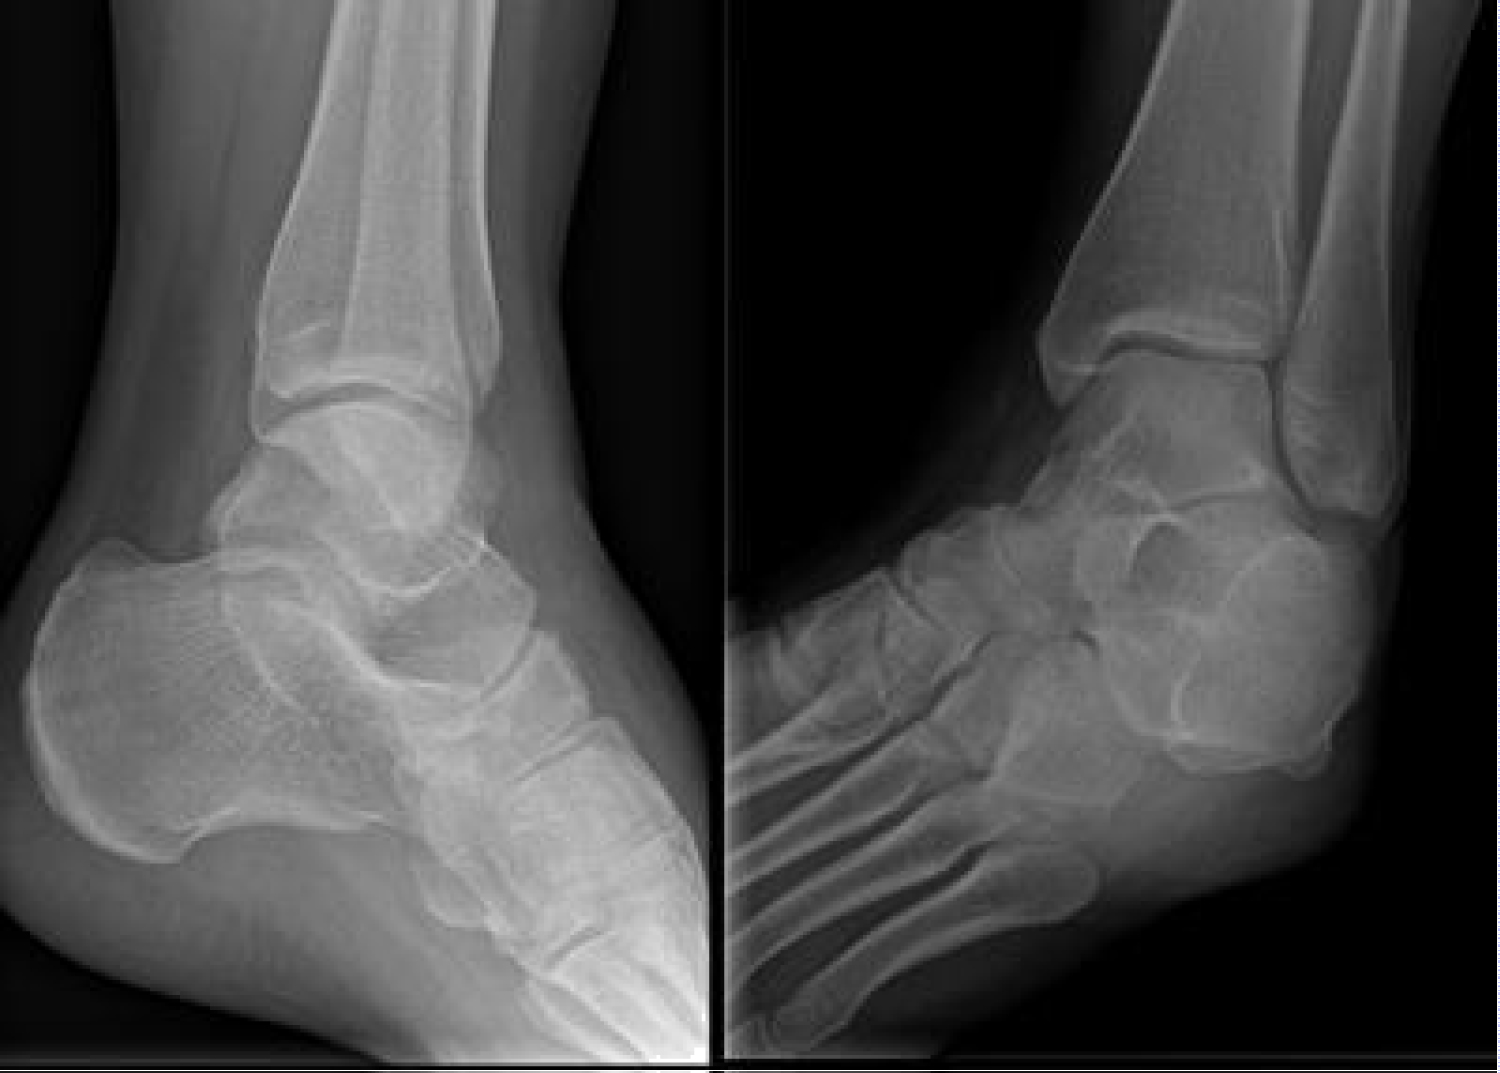

We present the case of a 21-year-old woman with no significant medical history. She was a non-smoker and worked in a supermarket. The patient suffered from an inversion trauma of her left ankle in December 2014. Her clinical symptoms where described as a painful, swollen lateral ankle. She did not tolerate weight bearing during first contact at the emergency department and plain radiographs taken at that time showed no fracture (Figure 1). The patient was diagnosed with a high-grade ankle sprain, the RICE principles where prescribed and the patient was sent home on crutches.

Figure 1: The initial radiographs from the left ankle taken at the emergency department in December 2014: To the left we see a medio-lateral projection and to the right we see the mortise-view into the talo-crural joint. These radiographs were protocoled as normal without posttraumatic injuries. A closer look however to the anterior process of the calcaneus shows a small avulsion. This is easily missed if not specifically looked for. View Figure 1